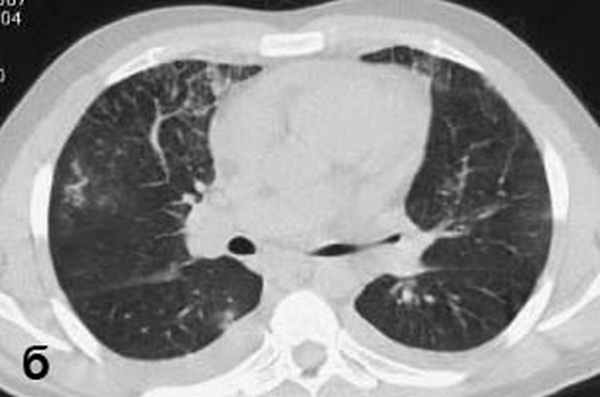

Больной С., 33 г., по профессии электромонтажник, поступил в НМХЦ им. Н.И. Пирогова 5 февраля 2007 г. с жалобами на одышку при незначительной физической нагрузке, кашель с трудноотделяемой мокротой слизистого характера, общую слабость, похудание на 10 кг, субфебрильную температуру тела. С 2000 г. у пациента диагностировали хронический ринит, синусит, полипоз носа. Для купирования затрудненного носового дыхания последние 3 года применял кортикостероидный назальный спрей. В связи с возникновением приступов удушья 2006 г. в НИИ аллергологии и иммунологии диагностирована бронхиальная астма среднетяжелого течения. Назначена терапия симбикортом с положительным эффектом. Ухудшение состояния с декабря 2006, когда появились субфебрильная температура тела, приступы затрудненного дыхания, одышка при физической нагрузке, снижение аппетита. При КТ органов грудной клетки, выполненной амбулаторно 25.01.07г.: лимфаденопатия средостения (лимфоузлы до 2-2,5 см) с образованием конгломерата размером 38 х 40 х 50 мм (рис. 1), снижение прозрачности легочной ткани по типу «матового стекла» (рис. 2а), диффузное уплотнение интерстициальной ткани (рис. 2б), двусторонний гидроторакс. Заподозрена опухоль переднего средостения в связи, с чем пациент госпитализирован для морфологической верификации диагноза.

| Рис. 2. КТ грудной клетки: а - снижение прозрачности по типу “матового стекла“, б - диффузное уплотнение интерстициальной ткани. | |